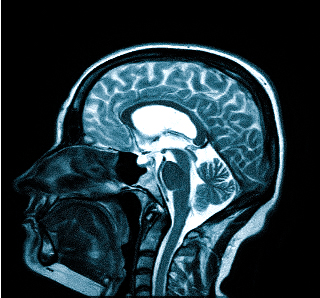

- МРТ (магнитно-резонансная томография) — это процедура, которая дает полное представление о состоянии исследуемой части тела пациента, а также о наличии или отсутствии того или иного заболевания. При МРТ четкие снимки получаются за счет обследования организма человека посредством воздействия магнитного поля.

Для проведения процедуры пациент ложится на стол-транспортер, который заезжает в томограф — сканирующее устройство. На время обследования пациент остается в трубе и должен сохранять неподвижность, чтобы картина получилась четкой. Процедура может занимать разное время — от 15 минут.